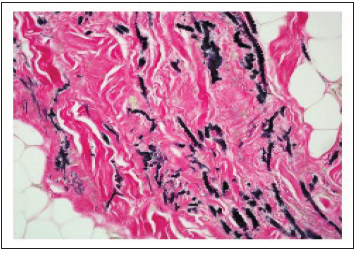

Elastofibroma is immune reactive to vimentin. Spindle-shaped cellular component is immune reactive to CD34. Elastic stains exemplify elastic fibres with a dense core and irregular margins (Figure 5). The tumour is immune non-reactive to S100 protein, desmin, smooth muscle actin (SMA) and p53 [2,3].

Figure 5:Elastofibroma delineating branched and unbranched elastin fibrils intensely stained dark brown to black with elastin stain.